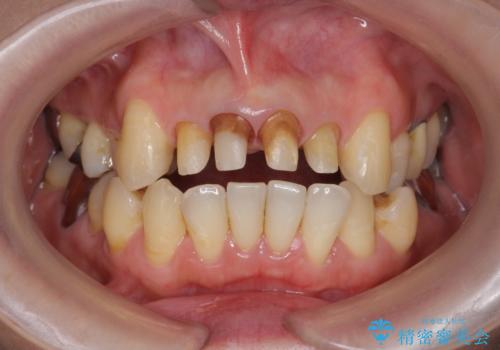

歯茎の黒ずみがきになる 前歯の見た目を改善したい

- クラウン周りの黒ずみが気になり、審美性の改善を求めて来院されました。

以前に治療した前歯クラウンは月日が経過することで劣化・歯肉の位置変化を引き起こし審美障害を引き起こしています。